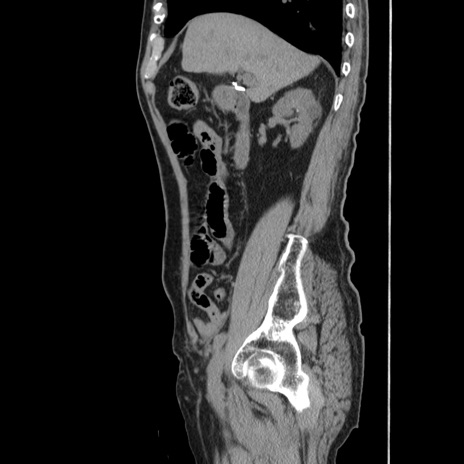

症例24(矢状断像)

【症例】80歳代男性

【主訴】左側腹部痛、嘔吐

【現病歴】本日早朝より左腹部に痛みあり。昼頃嘔吐認めたため、救急要請。

【既往歴】直腸癌(Mile手術)、胆摘

【身体所見】意識清明、BT 35.9℃、BP 221/93mmHg、SpO2 97%(RA) 、腹部:左ストーマ周囲に限局性の腹部膨隆あり。 膨隆部自発痛・圧痛あり・軟。

【データ】WBC 7700、CRP 0.09